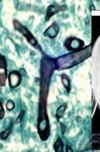

What organism is this?

A

Fusarium

Common in fungal keratitis (most commonly F. solani complex)

Macro and Microconidia